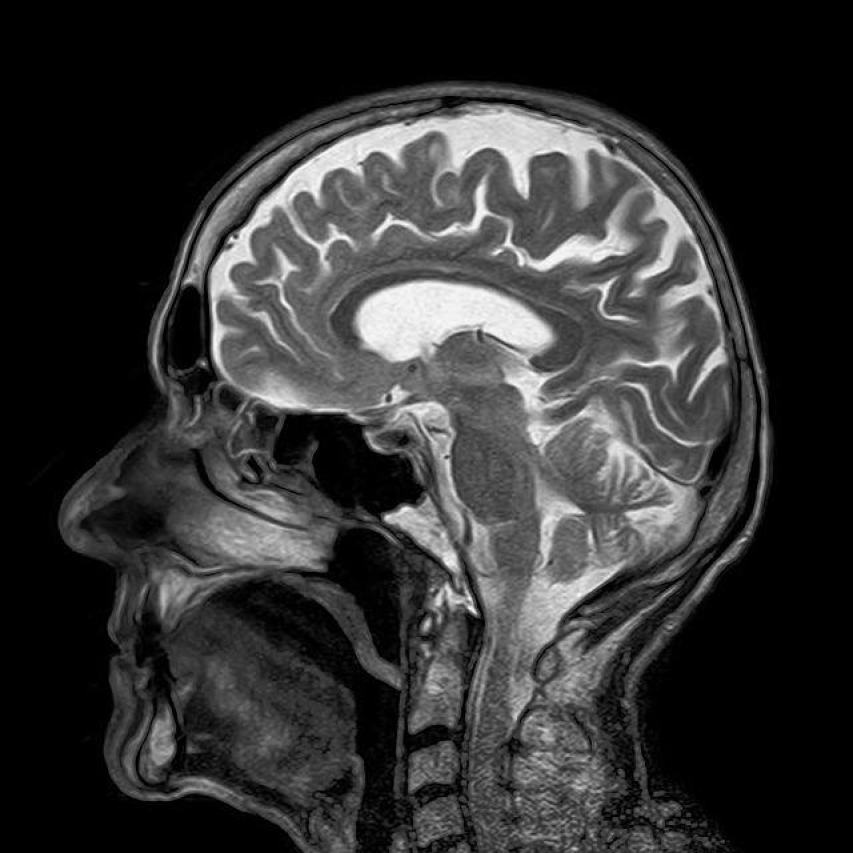

When it⁢ comes ⁤to understanding the inner workings of ⁤the human brain, few tools are​ as powerful ⁢and revealing as the Magnetic Resonance Imaging (MRI) scan. The ability to capture detailed images of the⁢ brain’s structure and⁢ function has revolutionized the field of neuroscience and ‍provided invaluable insights into various neurological conditions. However, with⁣ the advanced technology⁢ and expertise required ⁤to perform a brain‍ MRI comes a significant cost. In this article, we will delve into ⁤the factors that⁣ contribute to the⁢ price of a brain MRI, explore the range of costs⁤ across different healthcare systems and discuss the potential financial implications for patients in need of this critical‍ diagnostic tool.